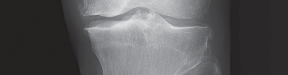

تُعد الأشعة السينية هي الأداة التشخيصية الأساسية لتقييم خشونة الركبة. يلتقط الأستاذ الدكتور هطيف صورًا للركبة من زوايا مختلفة، بما في ذلك صور الوقوف (Weight-bearing X-rays)، والتي تُظهر المفصل تحت تأثير وزن الجسم الطبيعي. تُظهر الأشعة السينية ما يلي:

- تضييق المسافة المفصلية: خاصة في الجانب الإنسي للركبة، مما يشير إلى تآكل الغضروف.

- تكون النتوءات العظمية (Osteophytes): وهي نتوءات عظمية صغيرة تتشكل حول حواف المفصل نتيجة للتآكل.

- تغيرات في كثافة العظام: مثل التصلب تحت الغضروفي (Subchondral Sclerosis).

- درجة الانحراف التقوسي: قياس الزوايا المحورية للساق لتحديد مدى التقوس بدقة.